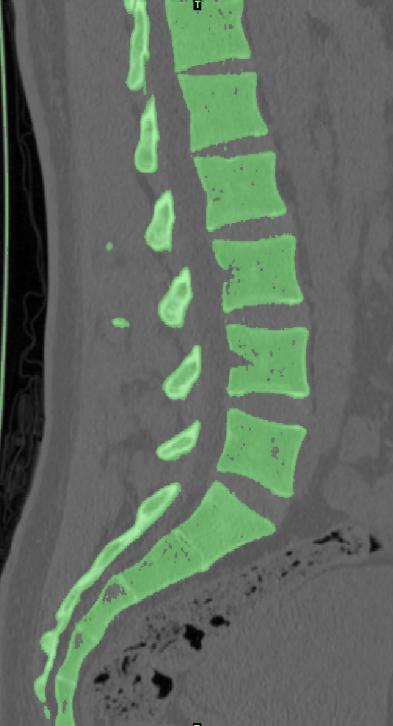

选取一名27岁青年男性志愿者在我院行腰椎螺旋CT扫描,扫描平面为:第十二胸椎椎体至尾椎末端,扫描厚度为0.625mm,得二维断层CT图像489张,以DICOM格式进行储存,导入计算机服务器。使用Mimics 19.0图像生成和编辑处理软件,直接读取 DICOM格式CT扫描数据进行三维重建,见 10。根据软件中不同的灰度值来区分不同的组织,用 Mimics 软件的阈值分割及区域增长功能画出腰椎(L3-5),不同的锥体用不同的颜色区分,最后用图像填充功能填补图像中的空洞,接着进行不同部位的三维重建,得到仅包含骨性结构(L3-5)的模型。Mimics 软件得到的模型以STL格式模型文件导入Geomagic wrap2017软件中,抹去模型钉状物和多余特征,然后对模型进行优化光滑处理,将L3-5光滑处理后的每个锥体进行复制,再将光滑后的模型在精确曲面中进行网格划分,并进行构建曲面片及修理曲面片,最后合成三维实体模型,见图11。此时将复制的每个椎体模型外层向部件内部偏移2mm,内部充当松质骨,外部的则定义为皮质骨,椎弓根后部统一由皮质骨组成。随后将模型以STEP格式文件导入Solidworks2020软件中生成L3-5实体模型零件,并在模型零件中构建椎间盘、髓核、上下终板和软骨,完成的实体模型,此时的模型为单纯的正常腰椎三维几何模型,各结构并未赋予材料属性与网格划分,见图12。将模型导入ANSYS软件中,随后对模型中皮质骨、松质骨、软骨、终板、纤维环、髓核赋予相应的材料属性赋值,尽可能地还原各组织材料的生理状况,提高模型的可靠性。定义关节突关节面为 Frictional,摩擦系数设0.1。在connections中建立spring模块,模拟前纵韧带、后纵韧带、黄韧带、棘间韧带、棘后韧带、横突间韧带及关节囊韧带,各韧带对应刚度赋值。建立完成后,对模型进行mesh操作构建网格,见图13。 undefined

10  Mimics                                                                             11  Geomagic